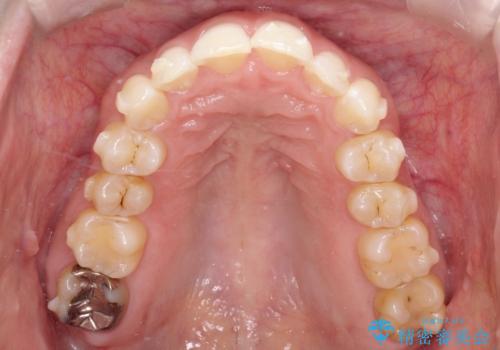

【インビザライン】前歯の凸凹を治したい。

- 前歯の凸凹を主訴に来院されました。

深い噛み合わせも同時に治療を行う計画を立て、インビザラインを使用して歯並びの改善を行うことができました。

叢生改善のために遠心移動とIPRを行なっています。